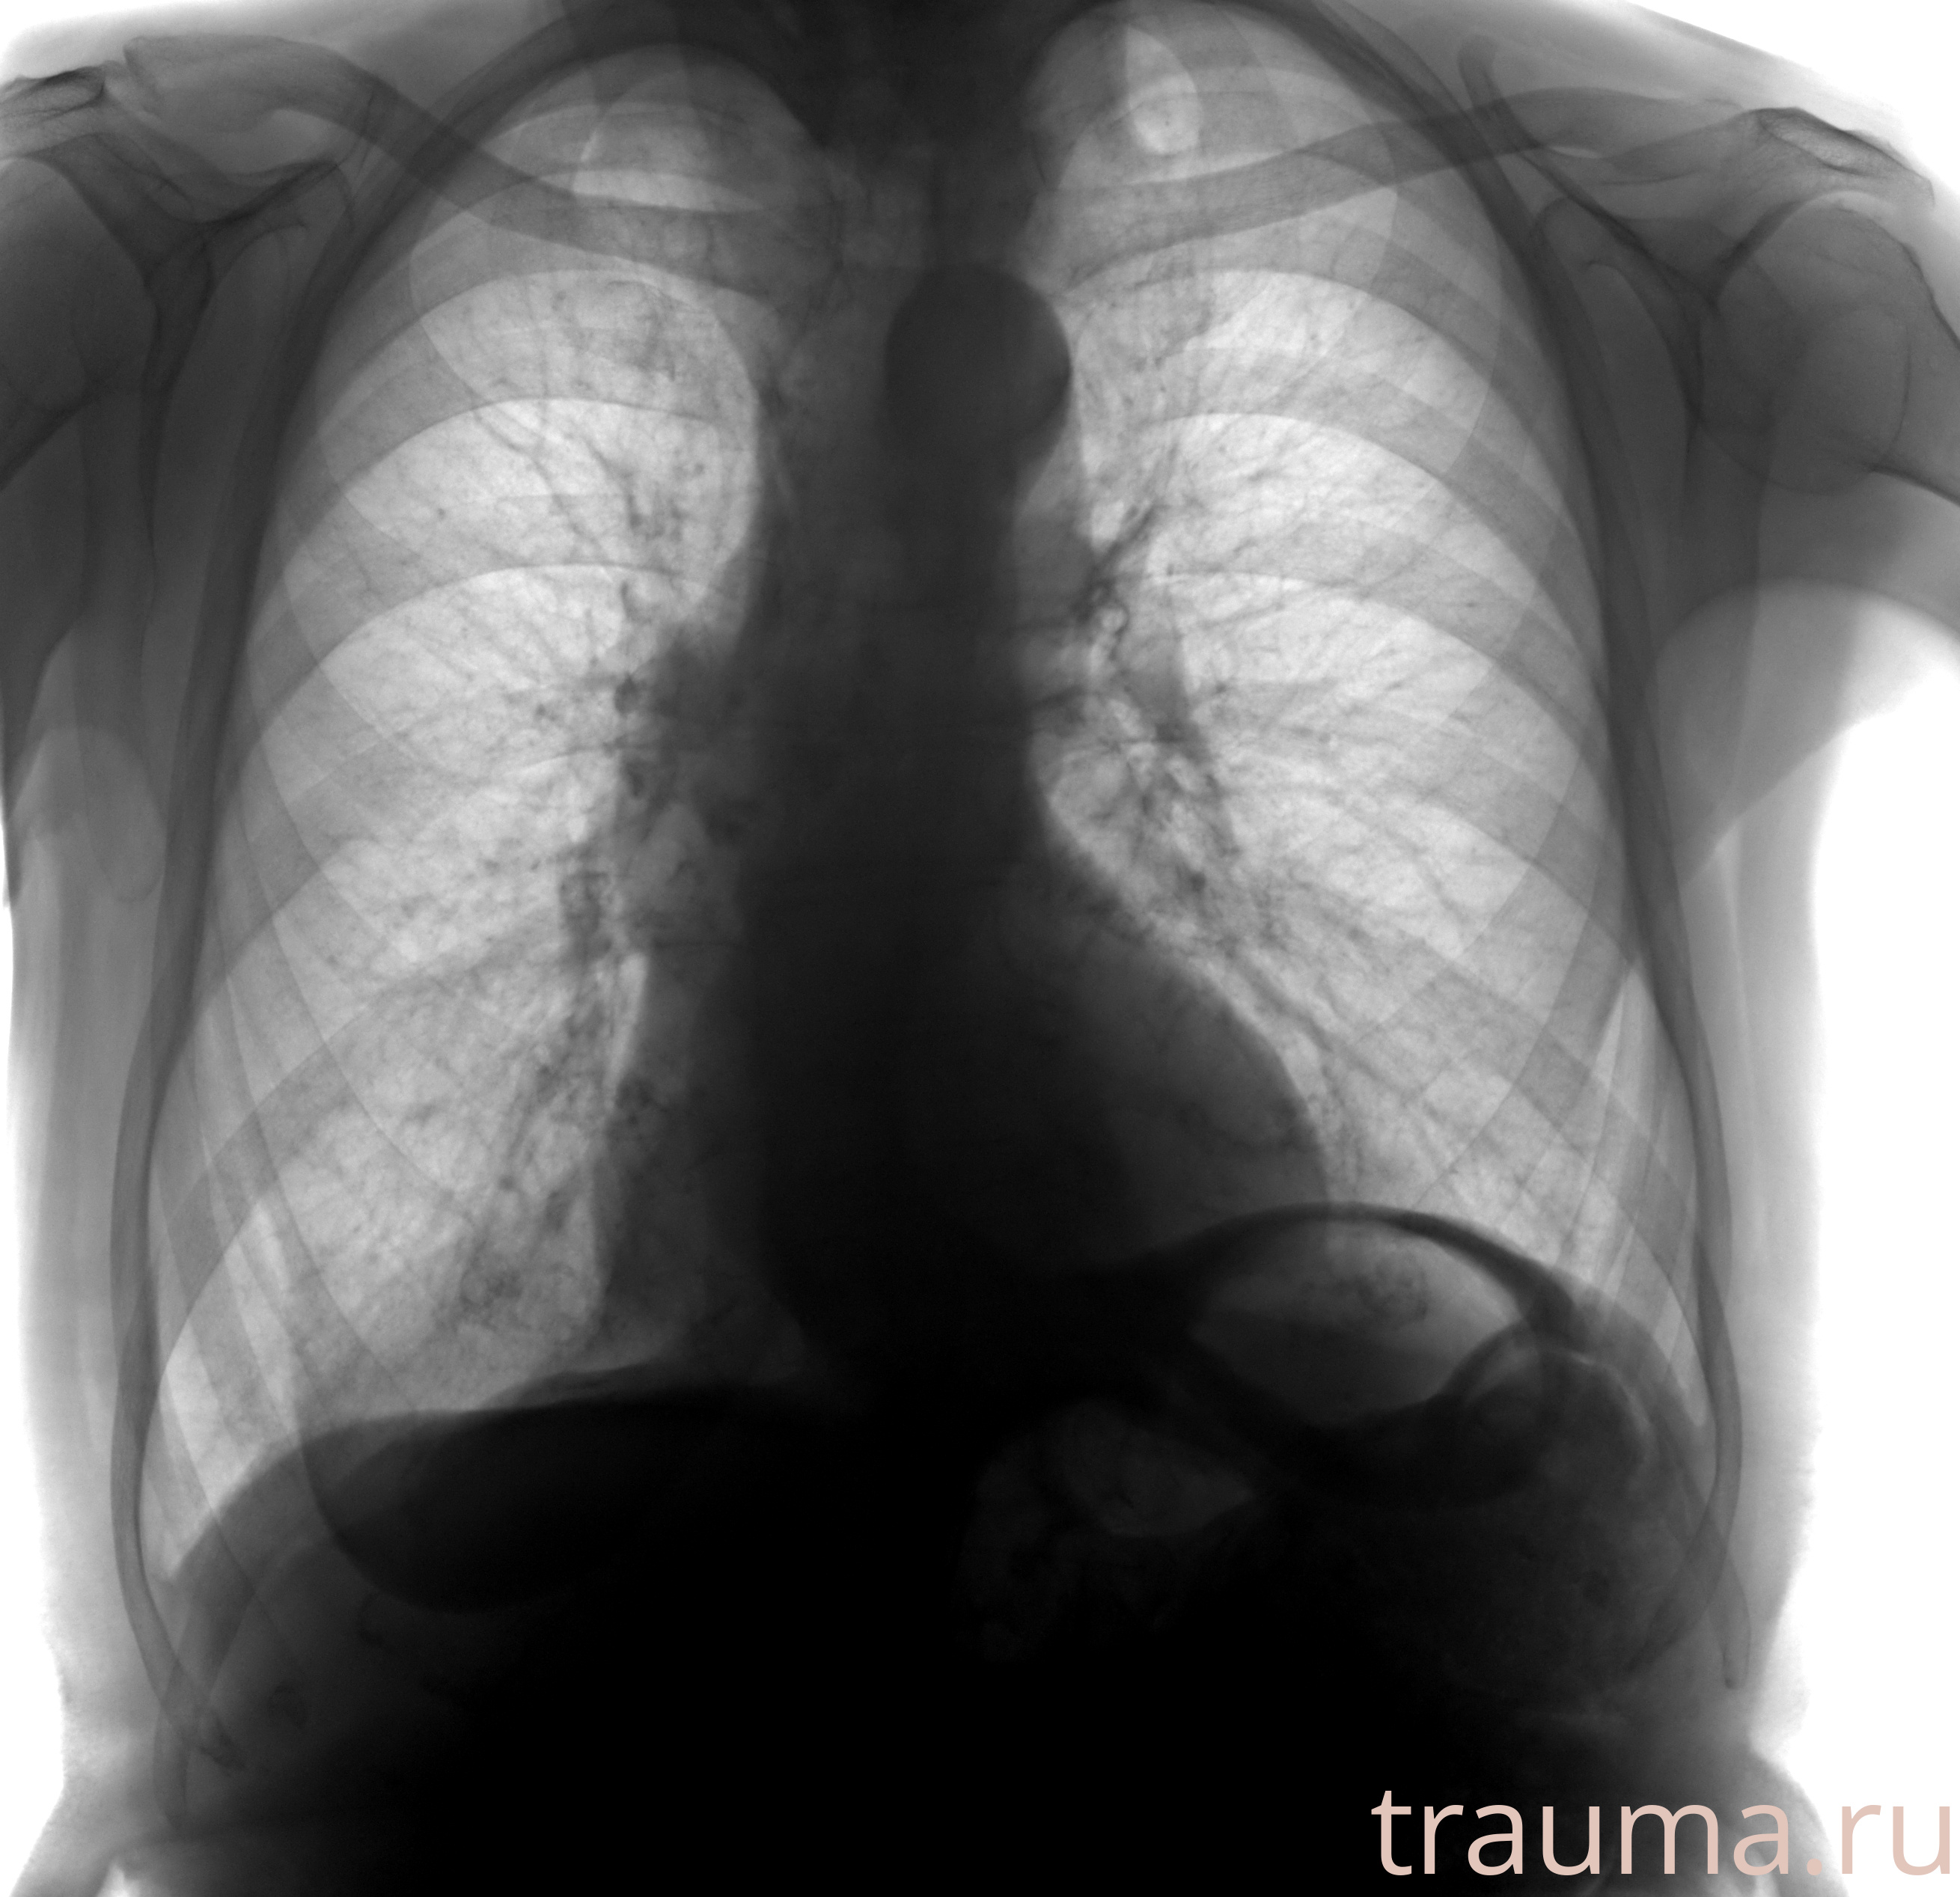

Рентгенограммы

Рентген на дому: по вашему адресу приезжает врач-рентгенолог, травматолог-ортопед с мобильным рентгеновским аппаратом, проводит диагностику травмы или заболевания, делает необходимые рентгенограммы, дает рекомендации по дальнейшему лечению. Получить качественные снимки в домашних условиях возможно благодаря уникальной методике, разработанной МосРентген Центром для института  Склифосовского

при переломе шейки бедра и пневмонии от компании МосРентген Центр - партнера Института имени Склифосовского